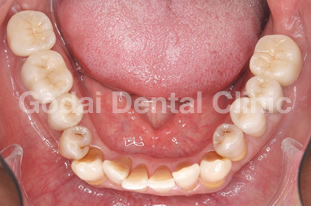

患者様は20代男性、虫歯の治療をしたいことと、歯並びを改善したいという主訴で来院されました。歯医者は10年以上ぶりですが、虫歯も歯並びもしっかり治したいという希望を持っていました。久しぶりの歯医者ということもあり、まずは歯磨きの仕方から改善していきました。歯垢をブラッシングで除去できるようになったところで、虫歯の治療を開始しました。歯並びが悪いこともあり、多くの歯に虫歯が見つかりました。患者様の年齢と歯質の保存を優先し虫歯の治療はコンポジットレジン修復を行いました。また下の親知らずが横向きに生えていたため、左右の親知らずの抜歯を矯正前に行いました。

歯ブラシの改善と虫歯の治療、親知らずの抜歯が終わったところで、矯正治療へ移行しました。患者様は健康な歯を抜きたくないという希望を持っていたので非抜歯の治療計画を立てました。まずは上下顎ともに拡大装置を用い歯列の拡大を行いました。その後、アライナーを使ったインビザライン矯正治療へ移行し、歯並びの修正と咬み合せの確立を行いました。拡大装置を使っている際は、口内炎や話しずらさなどがあったそうですが、インビザライン治療に移行してからは痛みも話しずらさもなくなり快適に過ごせたそうです。もともと多くの虫歯があったため矯正中の虫歯が心配でしたが、インビザライン矯正治療を選択したことで、新しい虫歯を作らずに治療を終えることができました。

歯並びを改善したい場合でも、歯磨きの確立、虫歯の治療、親知らずの抜歯など矯正前に治療が必要な場合もあります。ただ矯正前の治療をしっかりと行うことで、矯正治療の結果がより良いものになりますし、治療もスムーズに進みます。最終的に患者様にとって最善の治療になるよう心がけて治療を行っています。口の中が心配な方は、いつでもご相談ください。

治療前1

治療後1

治療前2

治療後2

治療前3

治療後3

治療前3

治療後3

治療前3

治療後3